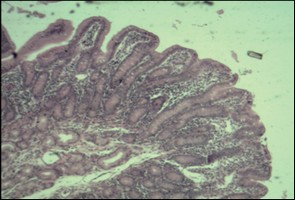

Foto N°1: Corte histológico del segmento duodeno de un lechón de 25 días de edad, el consumo diario de ración en la primera semana pos-destete (CRD) fue de 169 gramos/día. Como se observa en la foto, hay una atrofia de vellosidades lo cual afectara los procesos de digestión y absorción que ocurren en los diferentes segmentos del intestino. (Lescano et al., 2013- Journal of Animal Science)

El desarrollo del sistema digestivo de los lechones está en función de la cantidad y calidad de alimento consumido en los primeros días posterior al destete, por este motivo Lescano et al., (2013) realizaron un ensayo en la Universidad Federal de Viçosa, Brasil y observaron que la morfometría (altura vellosidad y profundidad de cripta) del intestino delgado de lechones desde los 18 a 25 días de vida presentaba mejora cuando los animales consumían mayor cantidad de un alimento de mayor calidad nutricional.

1. Cambios en la estructura y en la función del tracto gastrointestinal de los cerdos, ocurriendo atrofia de las vellosidades e hiperplasia de las criptas, con la disminución de la capacidad digestiva como consecuencia de la menor actividad de las enzimas dissacaridases y menor capacidad de absorción, con menor posibilidad de enfrentar los desafíos ambientales (SHAN et al. 2012; WU et al., 1996);